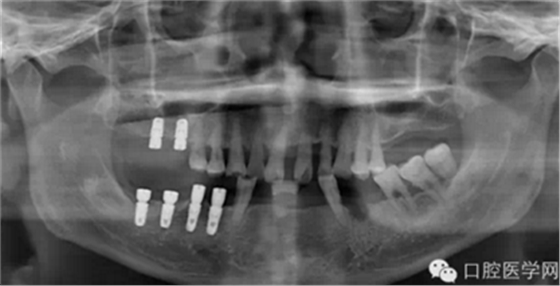

第四种,韩国奥齿泰种植体

第五种,瑞士士卓曼种植体(也称ITI种植体)